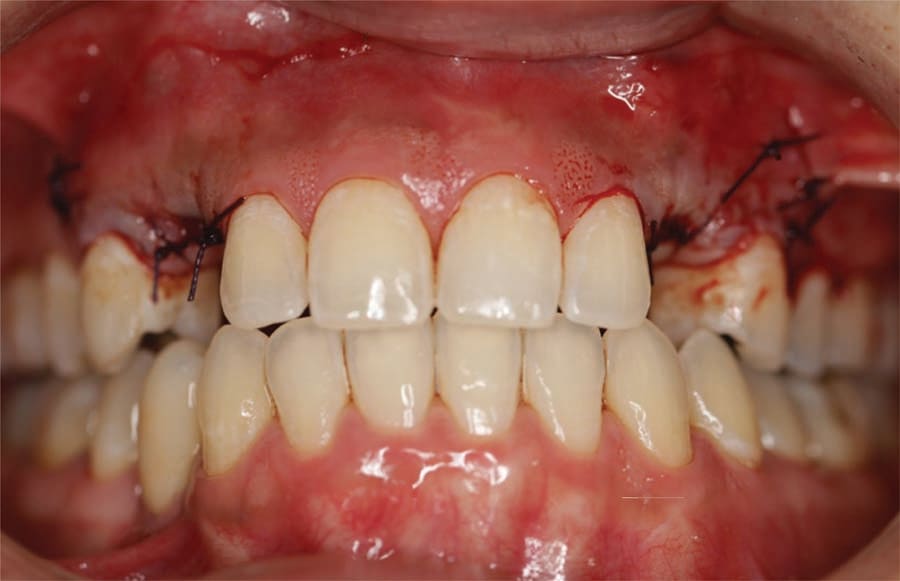

The patient presented for extraction of the deciduous canines and block grafting of the sites. Consent forms were reviewed with the patient and were signed. Local anesthetic was administered at the sites. Teeth C and I were extracted atraumatically, and a full-thickness mucoperiosteal flap was elevated at those sites (Figure 6). In this patient cortico-cancellous block grafts bilaterally were chosen (Puros® J-Block, ZimVie). The block of bone was contoured first on the cancellous alveolar side, with a football-shaped bone bur. The bone was placed in the recipient bed and was held firmly; the rest of the contouring was performed on the cortical side to allow the block to fit the site. Minimizing the thickness of the cortical bone also reduces the risk of dehiscence of the area. The cortical side was reduced significantly to allow adequate penetration of blood to allow integration and remodeling to native bone but leaving sufficient cortex to support adequate fixation. Next, using a 1.2-mm drill, the recipient site was thoroughly perforated to allow fresh bleeding and adequate penetration of the blood cells and growth factors into the graft. The graft then was firmly held against the recipient site, the 1.2-mm drill was used to place the screw hole, and a 1.2-by-10-mm screw was used to the secure the block graft into place (Figure 7). This was repeated at the left canine site (Figure 8). Particulate graft was not added so that the periosteum was in direct contact with the block to allow faster vascularization of the block graft. The periosteum underneath the flap was thoroughly scored and the flap was advanced to achieve tension-free primary closure and secured with 4-0 Vicryl sutures (Figure 9). The patient was seen for follow-up 1 week post-surgery.

A 31-year-old Asian female presented for a consult. Her medical history was reviewed, and no health issues were noted. She indicated her last dental visit was 2 years ago and her chief complaint was that her deciduous canines felt loose and she was unhappy with her smile (Figure 1). Examination noted fair oral hygiene with light generalized calculus and moderate bleeding in the posterior with 4 mm probing on the molars. The deciduous canines were present bilaterally in the maxilla which were grade 1+ mobile (Figure 2). Cervical caries was noted on both deciduous teeth on the facial and also the distal of the left deciduous canine (Figure 3). Tooth No. 28 (right mandibular first premolar) was noted to be missing. The patient indicated the missing bicuspid never developed and the deciduous molar was lost in her teens. Physical examination noted a concavity in the vestibule apical to the gingival margin at both canine sites. A panoramic and bitewing radiographs were taken to evaluate the dentition and arches (Figure 4). Radiographically it was confirmed that the permanent maxillary canines were not present nor was the mandibular bicuspid. Further, significant resorption of the roots of the deciduous canines was noted.